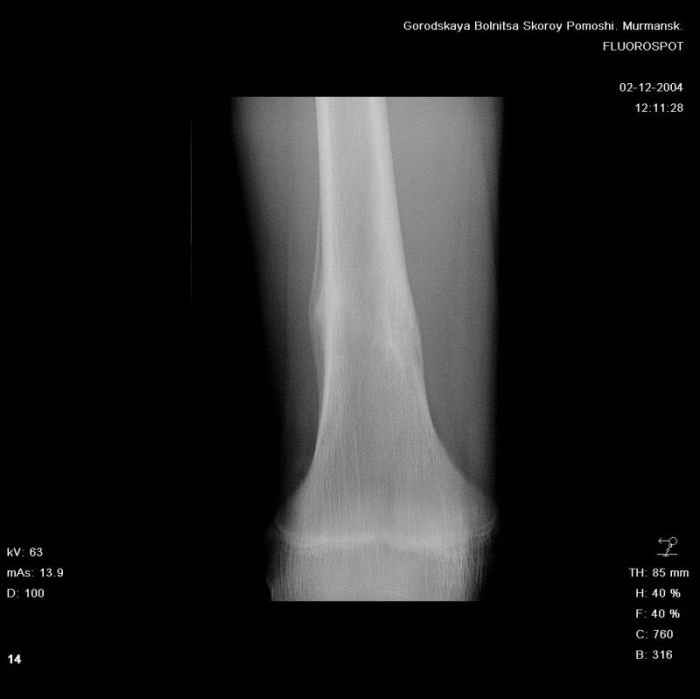

Анамнез практически никакой: в следствие травмы (растяжение связок коленного сустава) от 07.11.2004 выполнены Rg-граммы в травмпункте и обнаружено опухолевидное образование. Первичные Rg-граммы я не публикую, так как они заметно худшего качества, да и динамики за прошедшие три недели не отражают. Болевой синдром купирован в течение трёх дней. В настоящий момент мальчика ничего не беспокоит. Ходьба не нарушена, опухоль пальпируется с трудом по задней поверхности в н\3 правого бедра, пальпация безболезненна, объем движений в суставах правой нижней конечности полный и симметричный. Кожа над опухолью не изменена. В нашей клинике проведено дополнительное обследование: общие анализы крови и мочи, биохимия крови без особенностей. Выполнены Rg-граммы на цифровом Siemens обычные и продольные томограммы срезами 3-5 мм, а также компьютерная томография поперечными срезами по 5 мм. Прошу обратить внимание, что на приведённых томограммах видны две полости 10х15 мм и 15х60 мм. Также имеются два опухолевидных образований наслаивающихся друг на друга: уплощённое и вытянутое 10х100 мм и элипсовидной формы 15х30 мм. Это хорошо заметно на фото a_1.jpg c_1.jpg и d_1.jpg. Плотность внутри полостей 125% от плотности костномозгового канала, плотность наружного опухолевидного образования 55% от плотности кортикального слоя. Также отмечается линия перелома по центру наружного опухолевидного образования. Исходя из полученных данных мнения в плане диагноза несколько разделились от 1)сочетания кортикальной фиброзной дисплазии и латентно протекавшего маршевого перелома н\3 правого бедра до 2)остеосаркомы. В отношении первого варианта не сходится отсутствие клиники при переломе такой крупной кости как бедро, второй вариант вообще оставлю без комментария, ибо некомпетентен. Хотелось бы услышать мнения коллег, с удовольствием ознакомлюсь с любыми предположениями и замечаниями. С уважением, Александр Е. Клоков Отделение детской ортопедии и травматологии БСМП г. Мурманска.